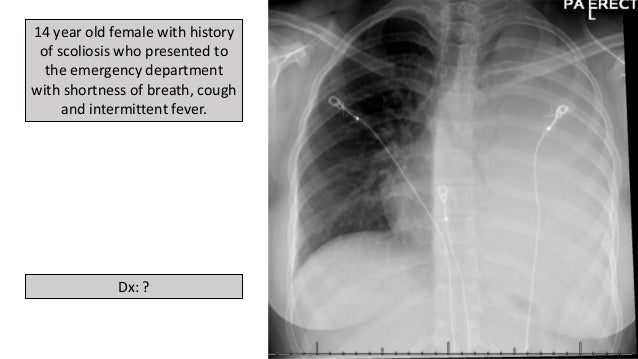

Get Pigtail Catheter Chest X Ray UK. Despite these and several other studies comparing pigtail catheters to chest tubes, further research, particularly prospective studies, need to be performed to. Clinical diagnosis of pneumonia was made in 18 (67%) infants.